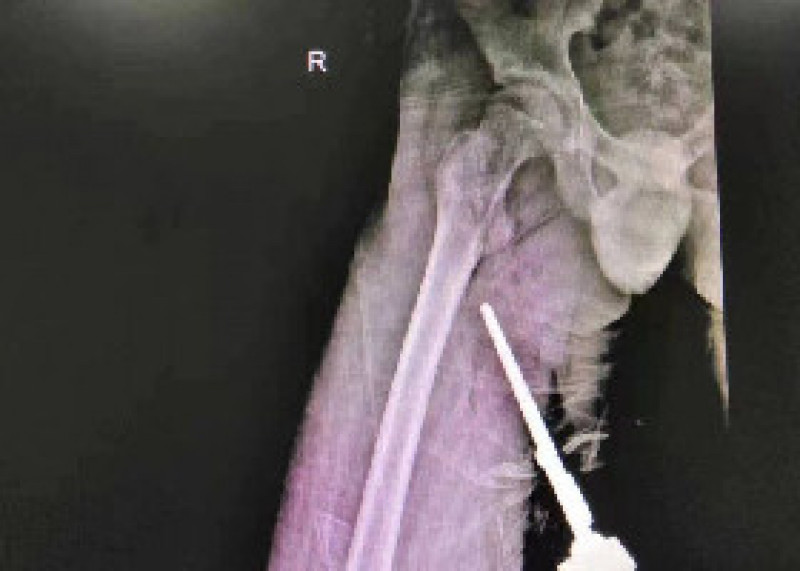

刚入院的小陈病情很严重,肖经难带领团队,查看患者病史并进一步完善相关检查,诊断小陈为颈椎椎体结核(颈1、2椎体)、寰枢关节半脱位,并发前后脓肿。病情已十分危急,随时可能出现呼吸骤停、四肢全瘫等严重后果。